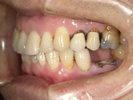

50代女性

![]() |

治療前 |

||

治療中。仮歯。 左上の奥にインプラント埋入。 噛みあわせ治療を行いました |

治療後 全体の歯で食事がおいしくできるようになったと喜んでおられました。 |